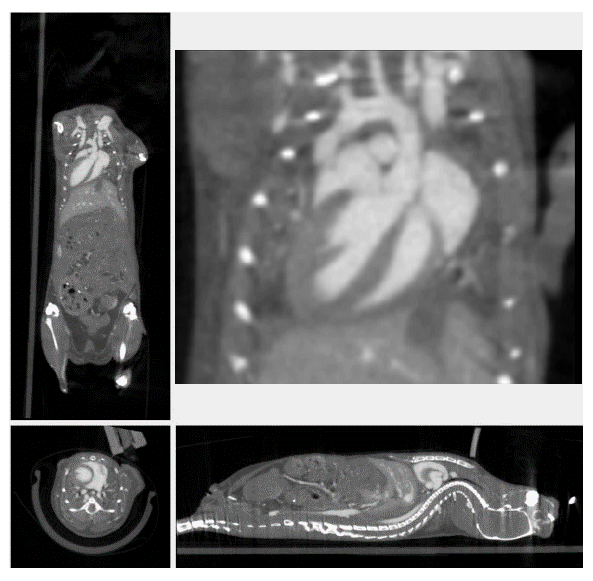

3、心血管研究

随着造影剂及心跳门控技术的发展, micro-CT成为临床前活体动物心脏研究的有利手段之一。micro-CT可以在相对短时间内获得心腔高分辨率的三维图像,可以对心脏的形态学和整体心室收缩指数进行量化,如心搏量体积、射血分数,心脏输出量等。收缩功能异常常见于心血管疾病中,尤其在早期临床表现中,而舒张功能的改善与生存时间的延长有关,因此,使用micro-CT评价舒张和收缩功能的评估是至关重要的,对心肺疾病的诊断、预后具有重要意义。

心脏门控成像

通过造影剂进行心脏结构成像和生理机能的监测。对心肌肥大,心律不齐和心脏射血分数进行测定。

心梗模型研究

随着干细胞技术的发展,用干细胞移植来进行心肌梗死治疗成为比较有前景的治疗方法之一。移植细胞的存活和功能依赖于新组织的血管形成。应用micro-CT可以对移植后的血管进行三维成像,发现移植体可以产生血管新生反应和冠状动脉重塑来灌注新的移植体。

冠状网络在移植组织和伤痕组织中的成像:

动脉为红色, 静脉为蓝色, 无法确定的为绿色,心肌组织中左侧冠状血管为黄色,移植体和伤痕组织中的为桔黄色。左侧冠状血管在移植和心梗的心肌组织中分支更为复杂。